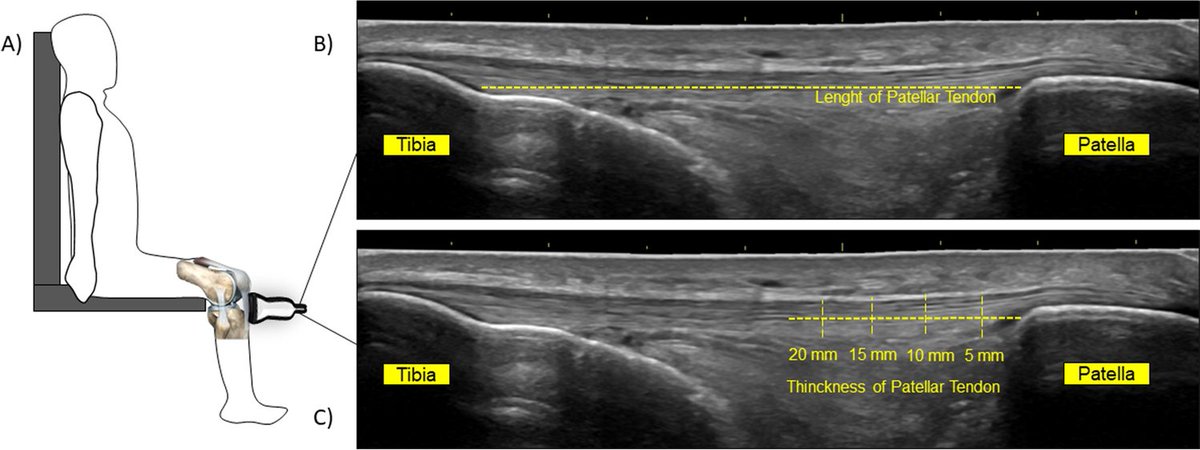

Ultrasound-guided preoperative skin-marking for deep inferior epigastric perforator flap surgery dlvr.it/TDdS6b